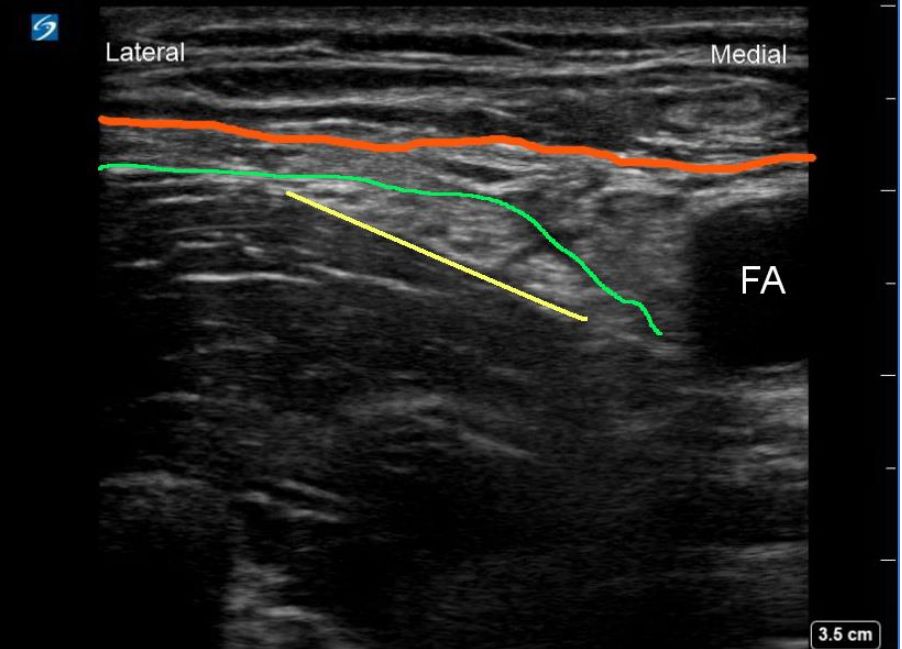

97. 在執行 femoral nerve block 時,需辨認 femoral artery 及 femoral nerve 附近的結構,以本超音波圖形為例,若 FA 代表 femoral artery,請問紅色線條代表那個解剖構造? (A) Fascia Iliaca (B) Fascia Lata (C) Fascia Cruris (D) Fascia Sartoriaca